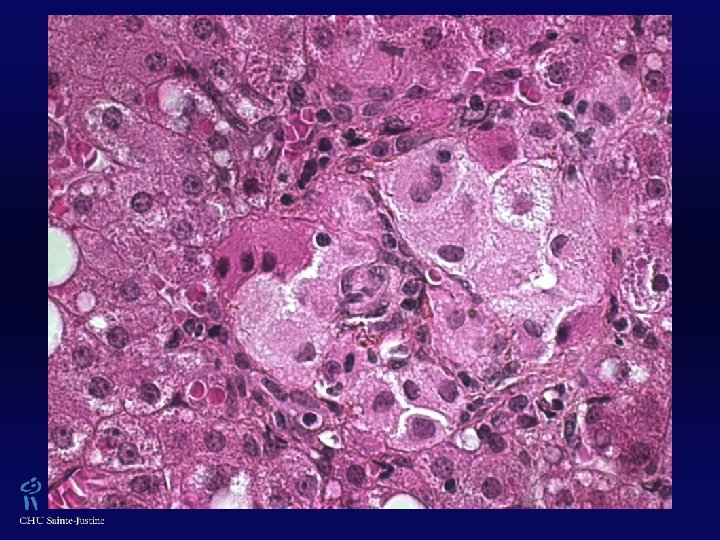

XGJ w Trois types cellulaires : w Cellules mononucléées w Cellules géantes mutinucléées, ± de type cellules de Touton (› lésions cutanées, absentes dans les formes jeunes) w Cellules fusiformes w ± Vacuoles cytoplasmiques, avec aspect xanthomateux w Éosinophiles 0/+++ w Vimentine +, CD 68 +, Facteur XIIa +, Fascine + w Protéine S 100 ± w CD 1 A -, absence de granules de Birbeck (ME)

Histiocyte Lysosomes contenant des inclusions denses

Hépatocyte Mitochondries normales Gouttelettes lipidiques Inclusions dans RE d’α-1 -antitrypsine